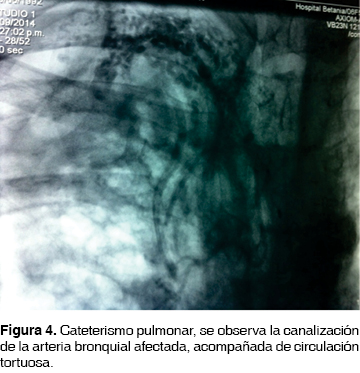

Joven de 22 años de edad, con diagnóstico de fibrosis quística desde los cuatro años con electrolitos en sudor positivo. Ha estado en tratamiento en el último año con broncodilatadores, esteroides inhalados y sistémicos de manera continua así como alfa dornasa y tobramicina inhalada por colonización crónica por Pseudomonas aeroginosa, secundariamente con uso de oxígeno suplementario de dosis de 3 a 4 litros por minuto y ventilación mecánica invasiva tipo Bilevel, aunado a tratamiento con rehabilitación pulmonar en los últimos seis meses. Ingresó al Servicio de Urgencias por presentar episodio de hemoptisis activa de aproximadamente 500 mL con el antecedente de cuadro de hemoptoicos y expectoración herrumbrosa de manera intermitente que requirió uso de carbapenémicos intravenosos en domicilio. Desde el punto de vista radiológico, se observó en la tomografía de tórax de alta resolución la presencia de múltiples bronquiectasias difusas bilaterales tipo quísticas generalizadas, con ausencia de parénquima pulmonar en lóbulo superior derecho (figuras 1, 2 y 3). Presentaba función pulmonar muy limitada con relación FEV1/FVC de 0.5 y FEV1 19%. Durante el evento se inició tratamiento con administración cuidadosa de vitamina k y dosis alternadas de etamsilato. Por el cuadro anterior y por persistir con el cuadro de hemoptisis fue llevado al área de hemodinamia pulmonar donde se le realiza cateterismo izquierdo con aortografía torácica y canulación selectiva de arteria bronquial derecha, la cual se observa con hipertrofia, tortuosa y con corto circuito arteria bronquial/arteria pulmonar (figura 4). Una vez localizada la arteria responsable de la hemoptisis, se procedió a embolizar con dispositivo tipo Amplatzer Plug IV (figura 5). Después del procedimiento evolucionó de manera satisfactoria con notable mejoría clínica. Se decidió egreso a domicilio para continuar con la terapéutica crónica.